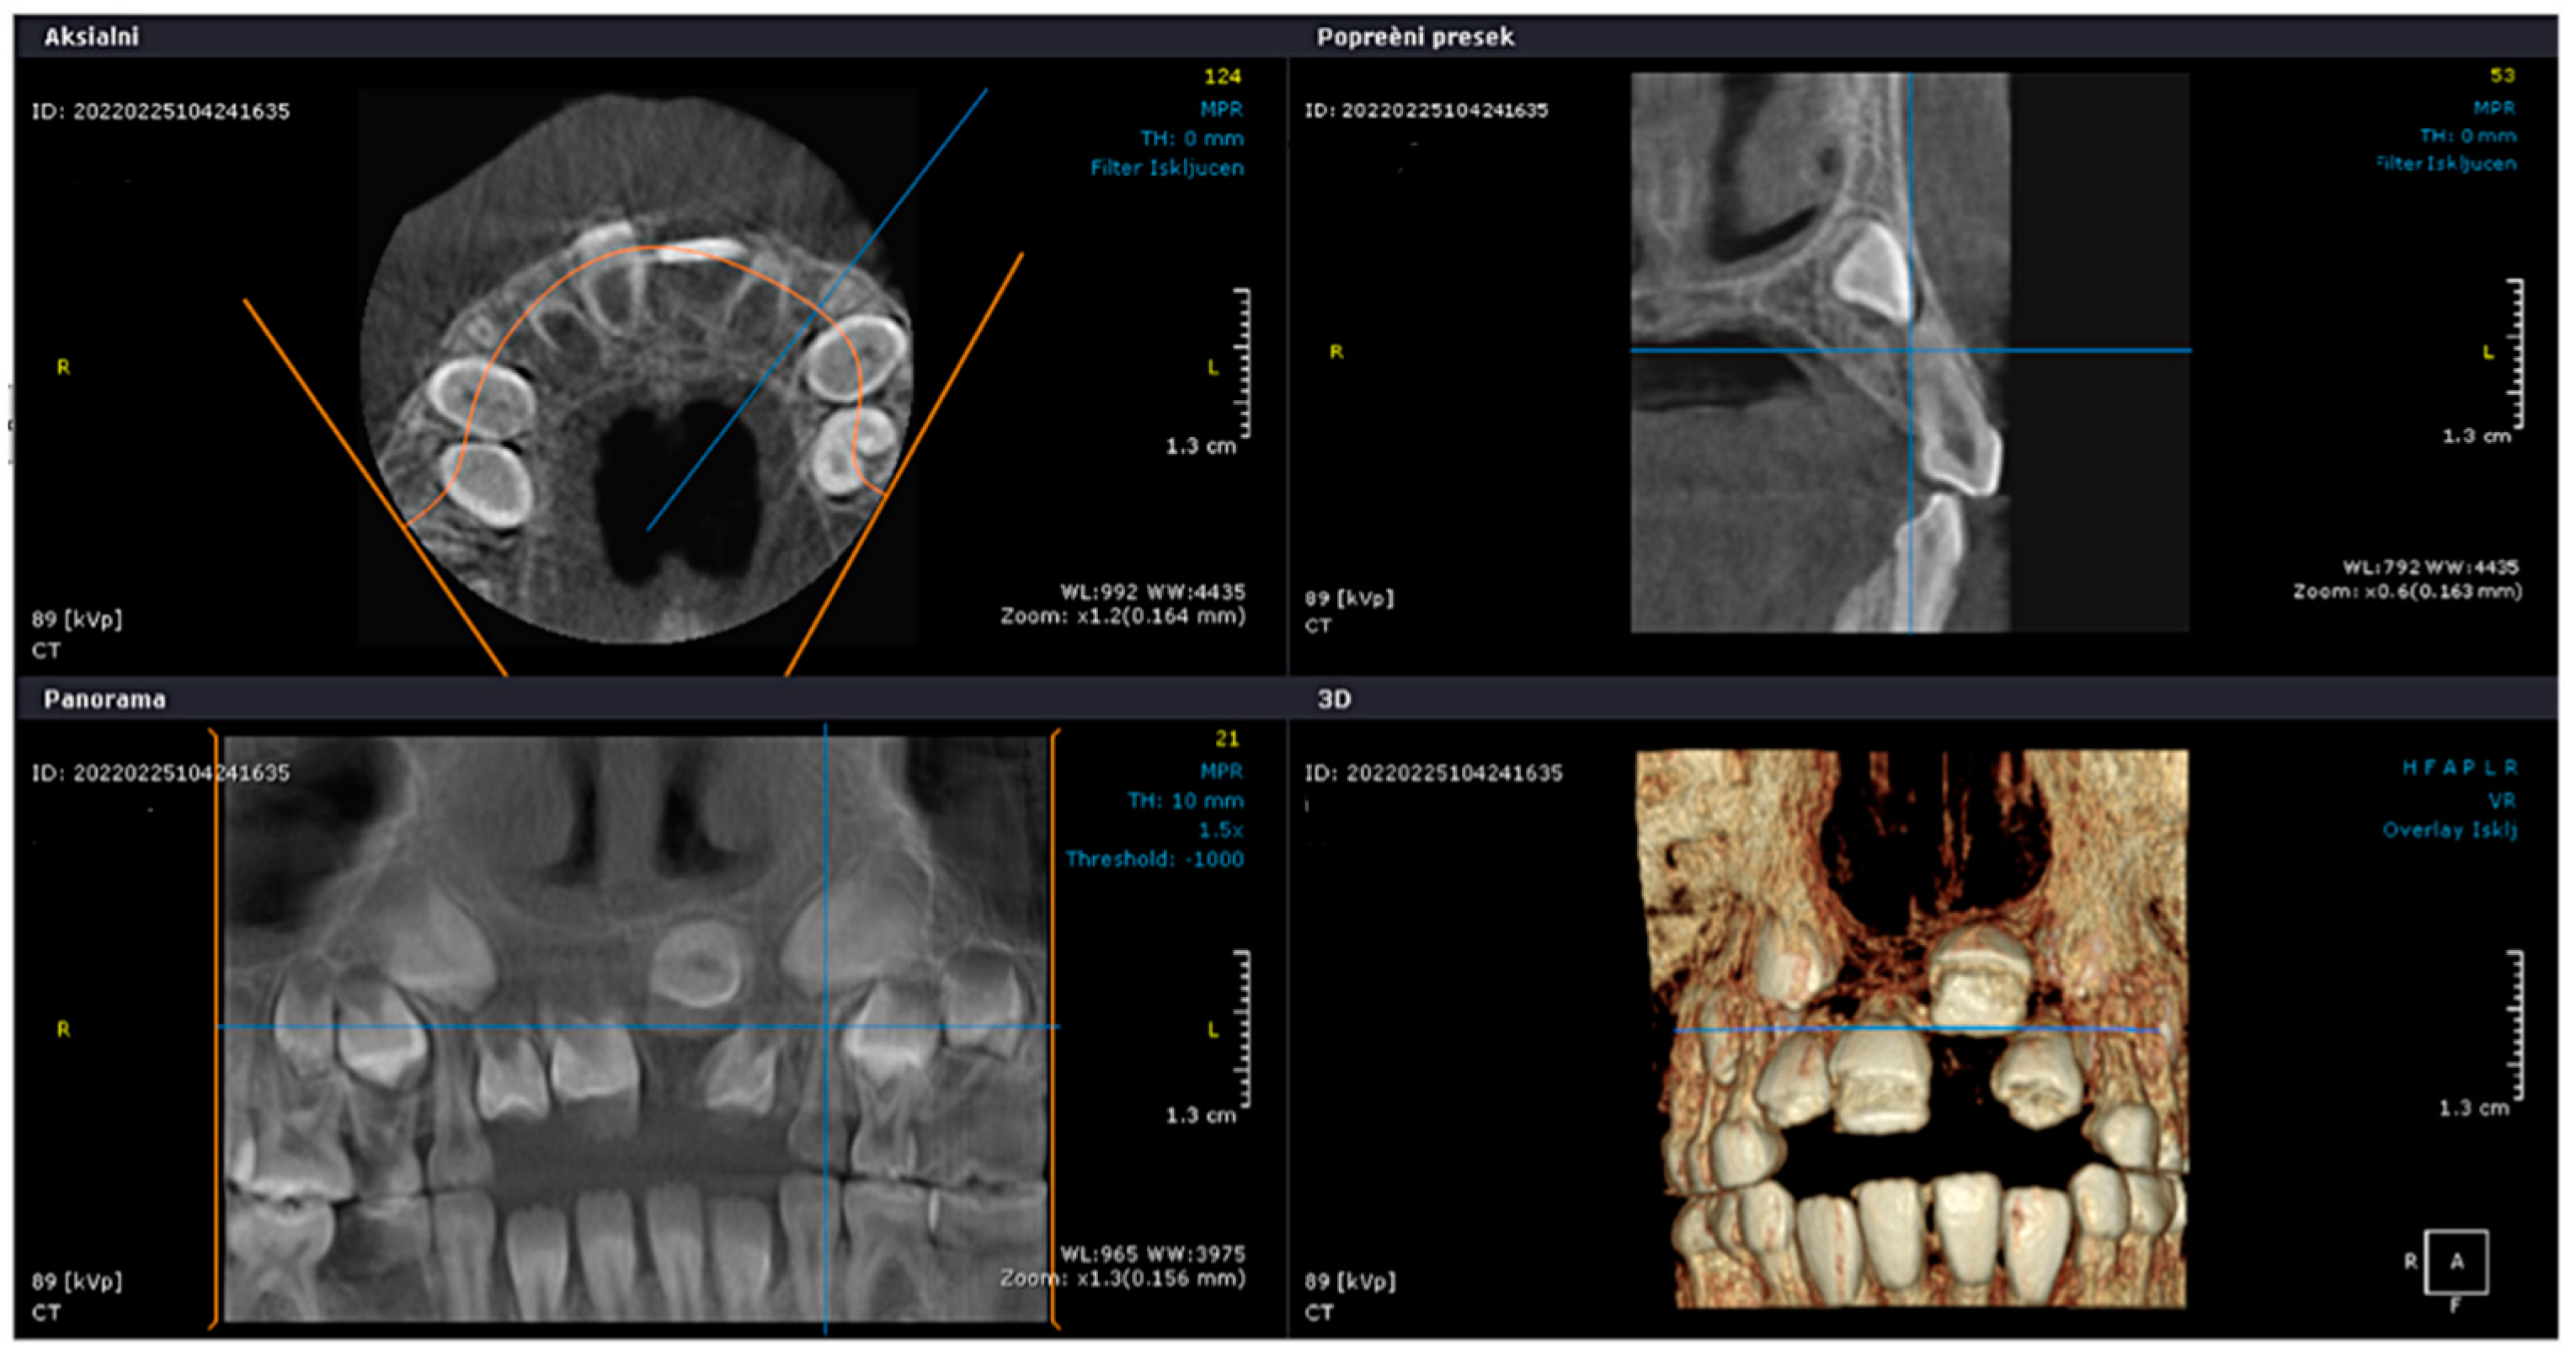

2. Case Presentation